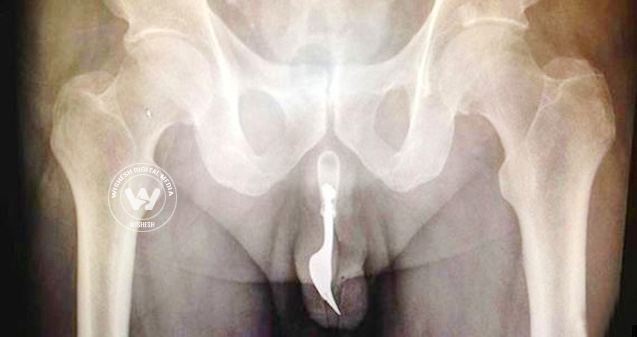

(Image source from: 70 year old man wedges fork in penis})

A 70-year-old Australian man had to be rushed to the hospital after he stuffed a fork into his penis.

According to a report published in the International Journal of Surgery Cases earlier this month, “The Canberra man was admitted to the hospital with 'bleeding urethral meatus' after he stuffed a 4-inch fork into his urethra in an attempt to achieve sexual gratification.”

The fork was later removed using forceps and "copious lubrication."